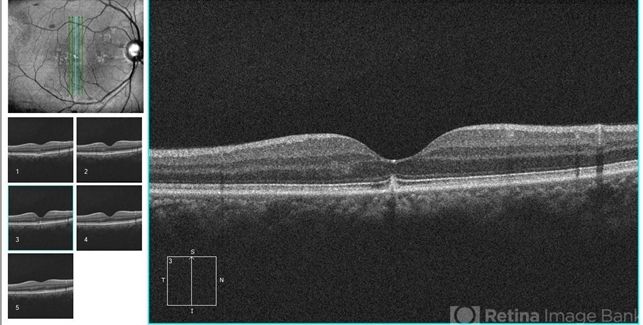

- optical coherence tomography (OCT), retinal pigment epithelium

- Eitae Kim, BOIM retinal center, Pureun eye hospital

Optical coherence tomography system

Cirrus, Zeiss - Description

- OCT image which shows peaked RPE layer at subfoveal region in retinal pigment epithelitis.